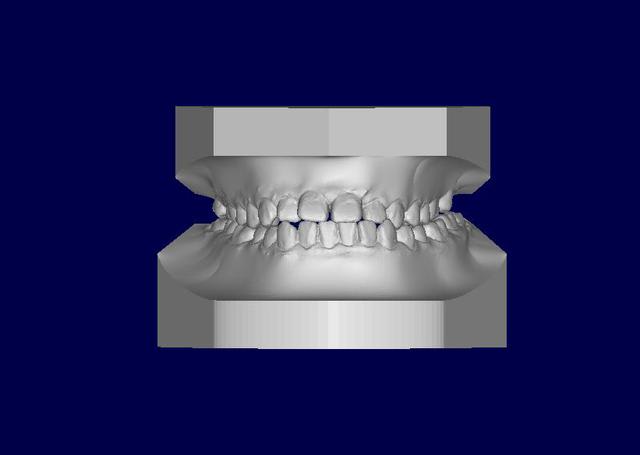

Patient asiatique, 25 ans, consulte car il veut corriger son crossbite bite antérieur localisé aux latérales et son crossbite secteur 2/3. Il aimerait également corriger son apparence générale, son profil notamment.

Classe III squelettique et dentaire.

Pas de shift à la fermeture.

Ci joints photos, ceph, modeles.